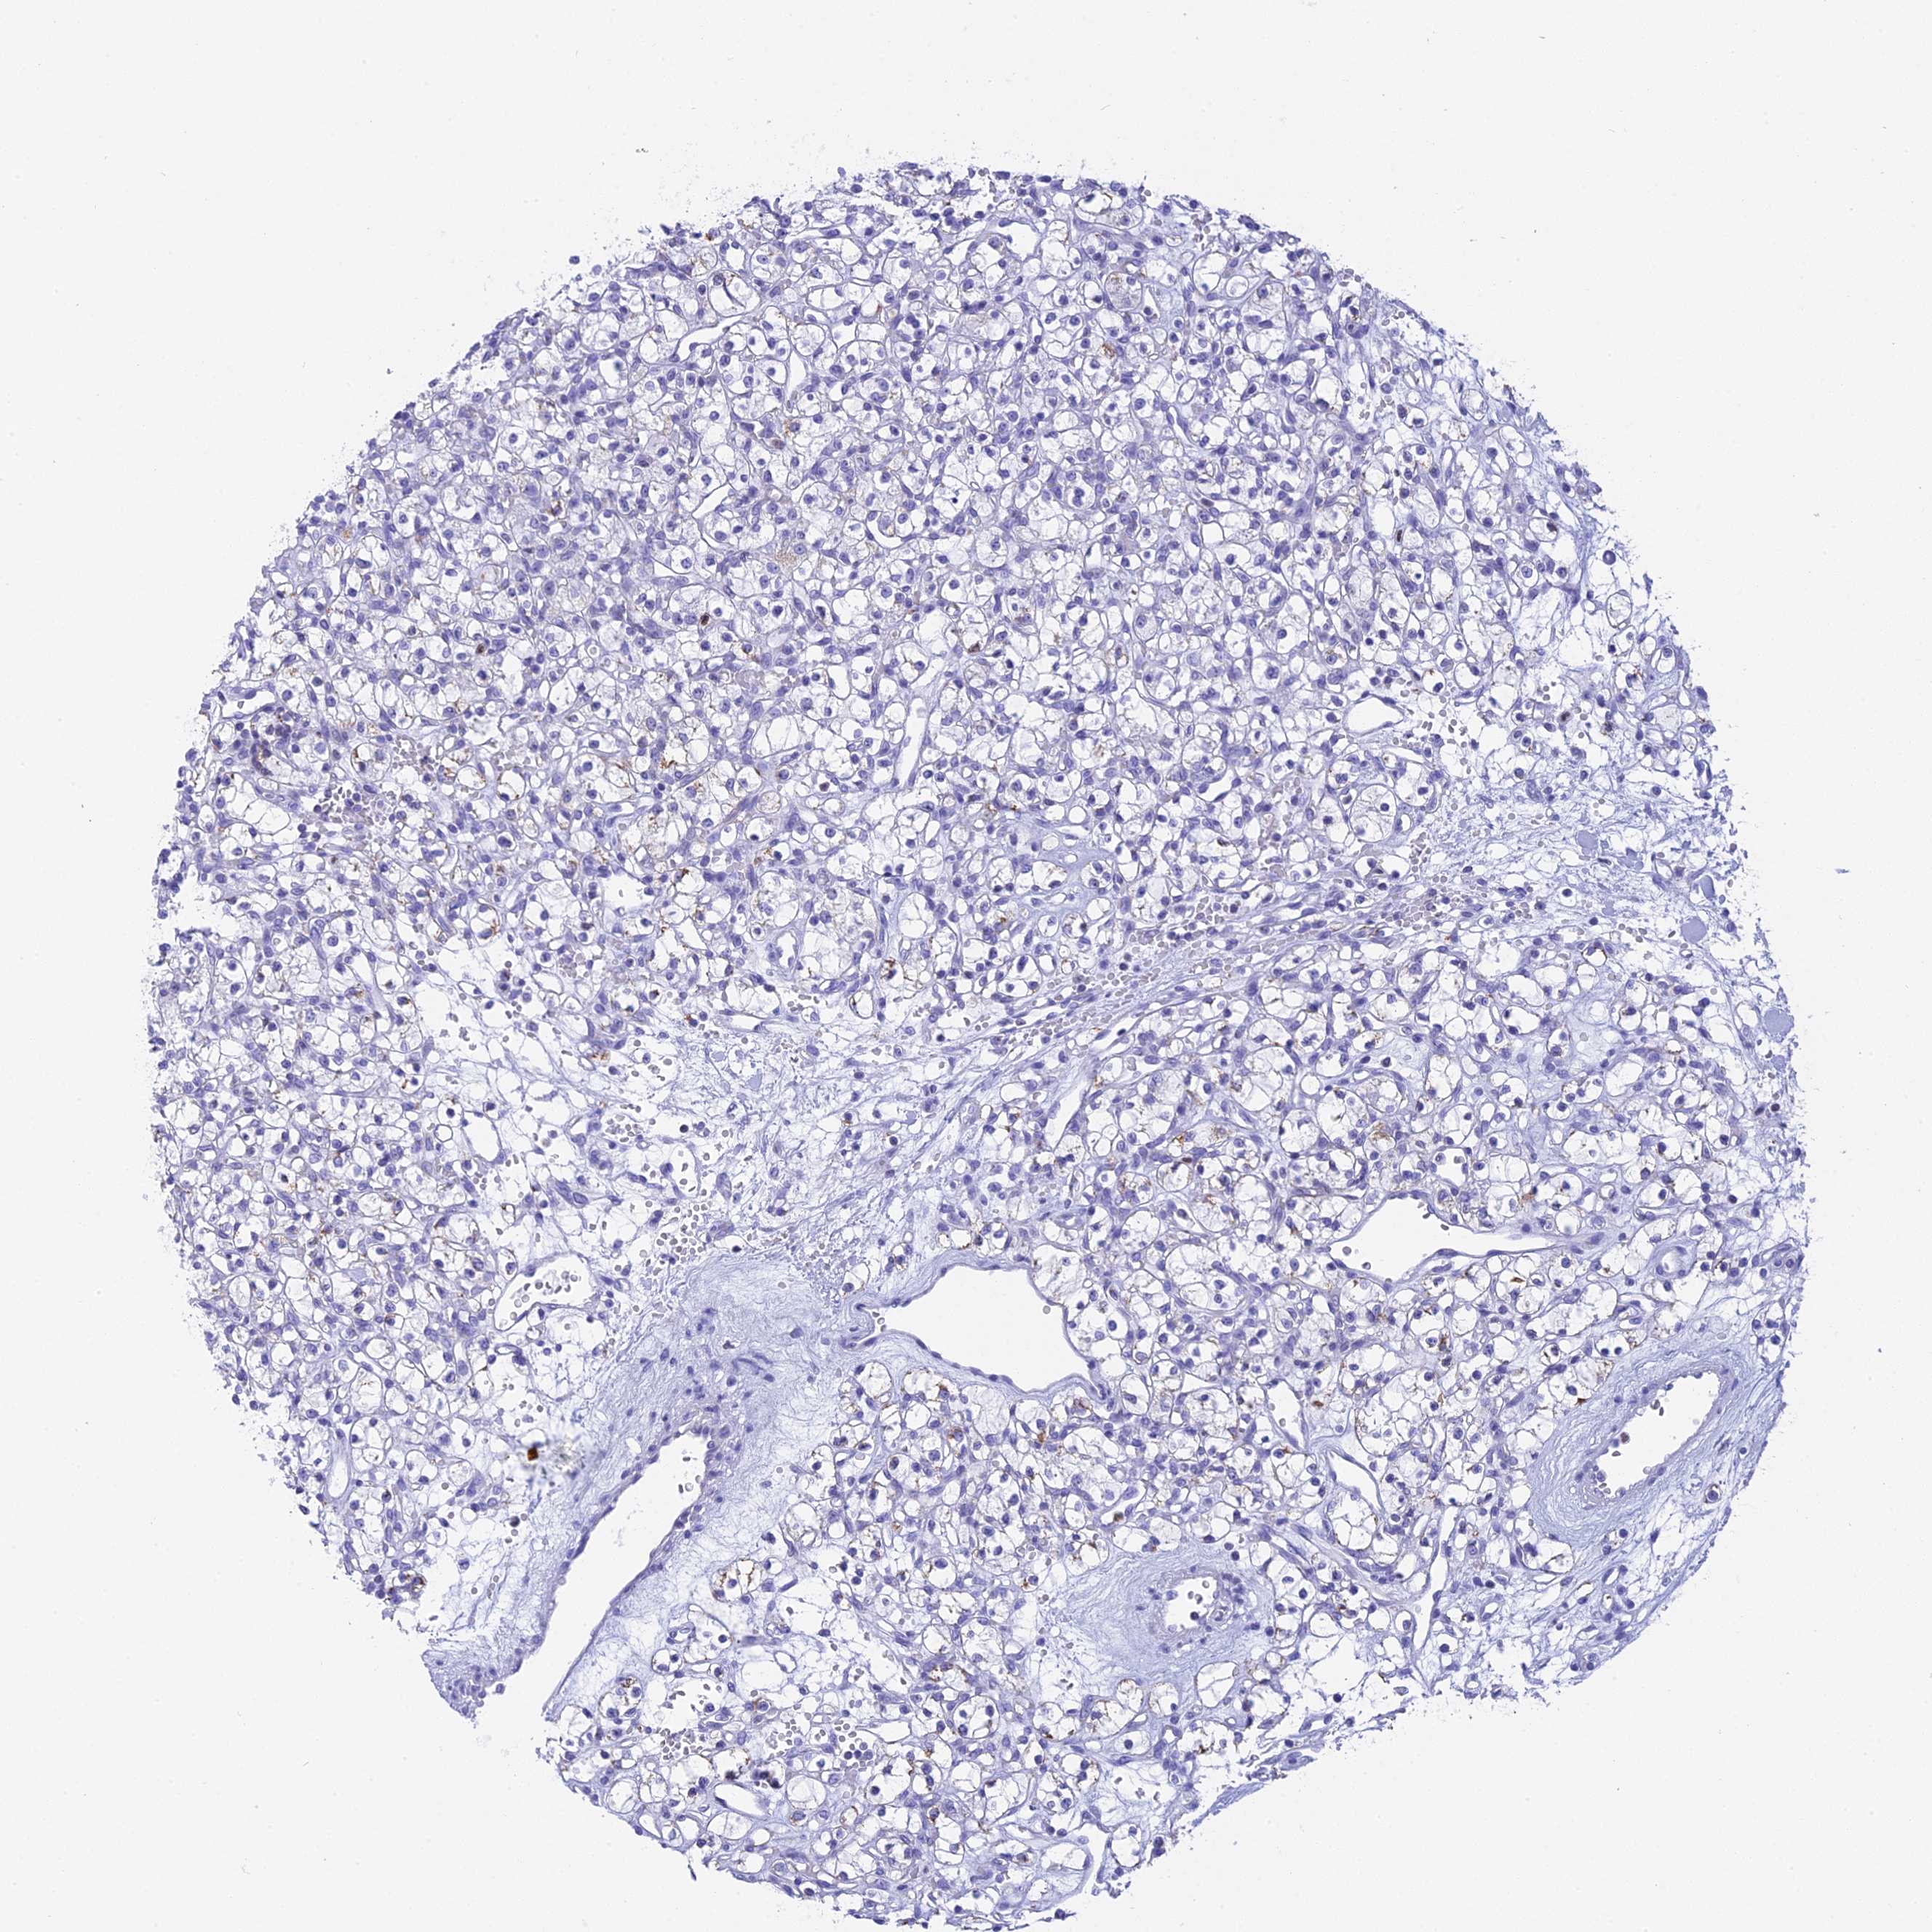

CANCER RENAL CANCER Show tissue menu

KICH TCGA KIRC TCGA KIRC VALIDATION KIRP TCGA PROTEIN RCC CPTAC PROTEIN EXPRESSION

ANTIBODIES

AND

VALIDATION